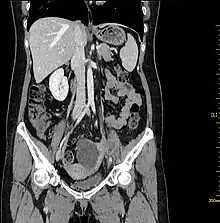

Computed tomography

Computed tomography (CT) scans is a diagnostic x-ray procedure that generates detailed cross-sectional images of the body, facilitating the detection of potential ovarian cancer spread to other organs.[16] While CT scans may not effectively visualize small ovarian tumors, they have the capability to detect larger tumors and evaluate their potential invasion into nearby structures. Additionally, CT scans can identify enlarged lymph nodes, signs of cancer spreading to the liver or other organs, and indications of an ovarian tumor impacting the kidneys or bladder. Although CT scans are not commonly used for biopsying ovarian tumors, they can be utilized in the biopsy of suspected metastases through a technique known as CT-guided needle biopsy.[16]

The difficulty in screening for SCC revolves around the creation of effective strategies with a positive predictive value. The timing aspect is crucial due to the lack of a specific timeframe for the onset of invasive disease or the interval stage between stage I and stage III carcinomas.[17] Ultrasound screening provides a detailed view of the ovaries, identifying morphologic changes as potential signs of malignancy. Key diagnostic factors include the presence of abnormalities, ovarian size, blood flow, and abdominal/pelvic fluid. The persistence of abnormalities after four to six weeks may decrease the occurrence of false positives. Screening protocols, often based on morphologic indices, utilize transvaginal ultrasound findings like cyst wall structure, septation, papillary projections, echogenicity, and ovarian volume to effectively detect malignancy.[17]